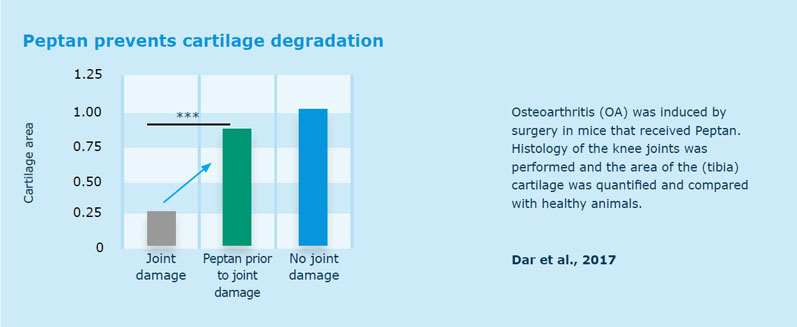

With regard to joint health, an in vivo study found that a daily dose of Peptan before cartilage damage resulted in cartilage preservation (Figure 1) and reduced inflammation (Figure 2) in mice, whereas in a randomised, placebo-controlled, double-blind clinical trial, elderly women with mild joint discomfort reported a significant reduction of painful symptoms, such as stiffness and pain, after oral intake of Peptan.6,8

These scientific findings showed this solution’s ability to increase the production of cells responsible for the building and maintenance of the cartilage matrix after just 3 weeks.

Figure 1: Oral intake of Peptan before joint damage preserves cartilage in mice